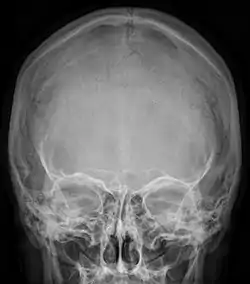

Radiograph of the skull showing an interparietal bone between the occiput and parietal bones

An interparietal bone (os interparietale or Inca bone or os inca var.[1]) is a dermal bone situated between the parietal and supraoccipital. It is homologous to the postparietal bones of other animals.

In humans, it corresponds to the upper portion of the squama of the occipital bone that lies superior to the highest nuchal line and is completely fused to the supraoccipital. However, in some individuals this portion remains separate from the rest of the occipital bone throughout life. In such cases, this separate bone is particularly referred as Inca bone. Inca bones in humans were first found in the skulls of contemporary indigenous peoples of the southern Andes as well as in those of mummies of the Inca civilization. Although the Inca bone was originally encountered as a variation in South American and Latin American cranial remains, the variation occurs in people from all geographic regions of the world and is by no means indicative of South/Latin American origin.